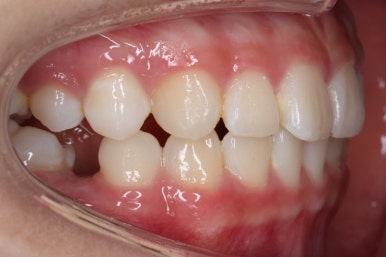

부산치아교정잘하는곳 처음 오셨을 때의 입안 모습입니다.

맨 우측 밑에 사진을 보시면 이가 하나 더 나와야 할 자리에(화살표) 앞뒤로 치아가 쓰러지면서 자리를 거의 없애버렸습니다.

따라서 이가 나올래야 나올 수가 없는 상태였습니다.

왼쪽 맨 위 사진을 보시면 아래 치열의 중앙이 한 쪽으로 쏠린 것을 알 수 있는데요. 역시 치아가 나올 자리가 없어지면서 치열이 쏠러버렸다는 것을 알 수 있습니다.